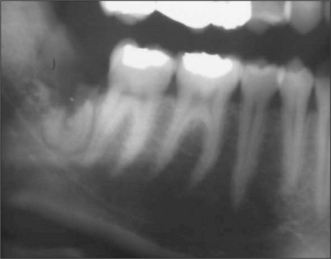

The radiographic examination of choice is a panoramic radiograph such as an OPT (Fig. 5.3), although periapical or oblique lateral views of the mandible may be taken as an alternative. When referring a case for treatment all recent relevant radiographs should be included to avoid further exposure to ionizing radiation.

image

Fig. 5.3 A mesioangular impacted lower third molar on the right and distoangular impaction on the left. (Note the unerupted third molars in the maxilla.)